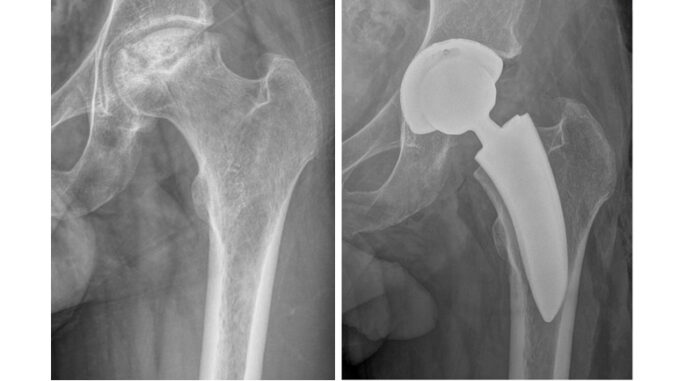

L’Ospedale di Perugia si conferma tra i centri di eccellenza della sanità italiana grazie all’introduzione di protesi d’anca rivestite in argento, una tecnologia che sta rivoluzionando la chirurgia ortopedica. La notizia, diffusa dall’Azienda Ospedaliera di Perugia, evidenzia come la struttura umbra abbia raggiunto risultati di rilievo, con oltre trenta interventi già eseguiti e un tasso di infezioni post-operatorie pari a zero.

Il dottor Bisaccia evidenzia che la sicurezza si accompagna alla funzionalità, offrendo una chirurgia più personalizzata e moderna. Accanto a questo programma, l’équipe ha avviato un progetto dedicato ai pazienti più giovani, con protesi a conservazione del collo femorale, anch’esse rivestite in argento. Questa soluzione consente di preservare una maggiore quantità di osso e di mantenere una biomeccanica naturale, risultando particolarmente indicata per chi soffre di artrosi precoce, necrosi asettica o displasia congenita dell’anca.